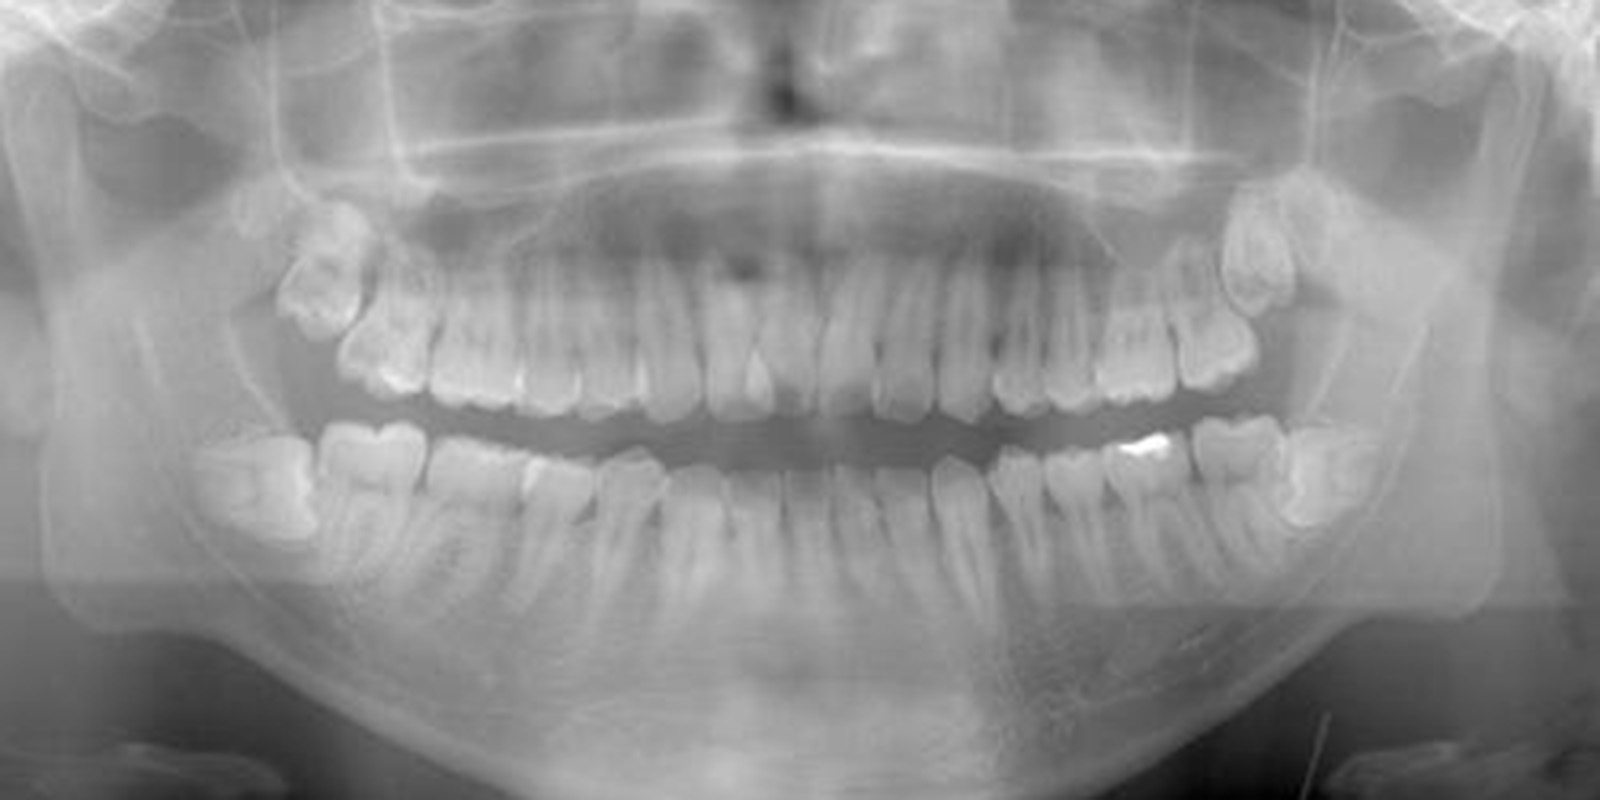

親知らずがあるレントゲン画像

ただ根の先に下顎管が触れているようなケースであれば2回で対応したりしますが歯の頭の部分が下顎管と触れているような稀なケース、親知らず周りが嚢胞になってしまっているケース、全身疾患がある方、外科処置が困難な方に関しては大学病院を紹介させていただくこともあります。

1. レントゲン、口腔内検査によって抜歯の可否を決める。